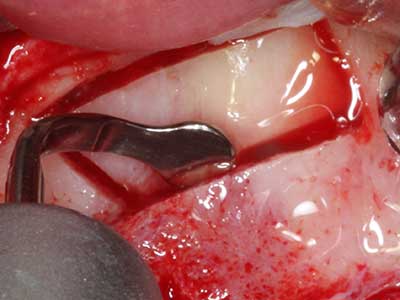

Bei der Knochenblockentnahme zeigen sich weitere Vorteile für die Piezochirurgie: Neben der bereits beschriebenen hohen Präzision bei der Osteotomie stellt sich gerade die Verwendung der dünnen Sägespitzen als besonders materialschonend heraus. Bei der Verwendung insbesondere von Lindemannfräsen sind mit deutlich höheren Entnahmeverlusten durch die dickere Instrumentenspitze zu rechnen (Lakshmiganthan, Gokulanathan et al. 2012). Die insbesondere bei retromolar entnommenen Blocktransplantaten notwendige basale Abtrennung wird durch speziell hierfür vorgesehene rechtwinklige Sägen erleichtert, so dass die Piezochirurgie als präzises, übersichtliches und sicheres Verfahren zur retromolaren Knochenblockgewinnung angesehen wird (Happe 2007) (Abb. 1-12).

Sollen chirurgische Eingriffe mit unmittelbarer Knochenbeziehung an empfindlichen Strukturen wie Blutgefäßen oder Nerven erfolgen, so bergen rotierende Instrumente ein erhebliches Potential an iatrogener Schädigung. Gerade bei Nervdarstellungen nach iatrogener Schädigung, oder aber im Zuge einer Nervlateralisation für resektive und rekonstruktive Eingriffe oder Implantatinsertionen können piezoelektronische Geräte hilfreich sein Knochendeckel zu präparieren und nervnahe Hartgewebsanteile zu entfernen (Abb. 17-20). Ein leichter Kontakt des Nervstrangs zur Piezospitze bleibt dabei in der Regel folgenlos – allerdings kann eine unvorsichtige Vorgehensweise mit sägeartigen Bewegungen bzw. Ansätzen bei noch vorhandener knöcherner Unterlage durchaus temporäre oder aber auch permanente Nervschädigungen verursachen. Das Risiko einer solchen Schädigung wird jedoch als wesentliche geringer eingeschätzt als unter Anwendung von Säge- oder Fräsinstrumenten (Pereira, Gealh et al. 2014).